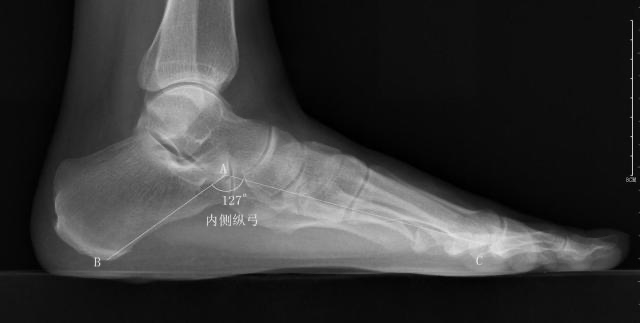

内侧纵弓

-

正常值:113°~130°

测量方法:从跟骨的最低点到距骨头的最低点作一条直线,再从距骨头的最低点到第1跖骨头最低点作一条直线,然后测量两条直线所构成的夹角

扁平足时内弓角增大,弓形足时相反